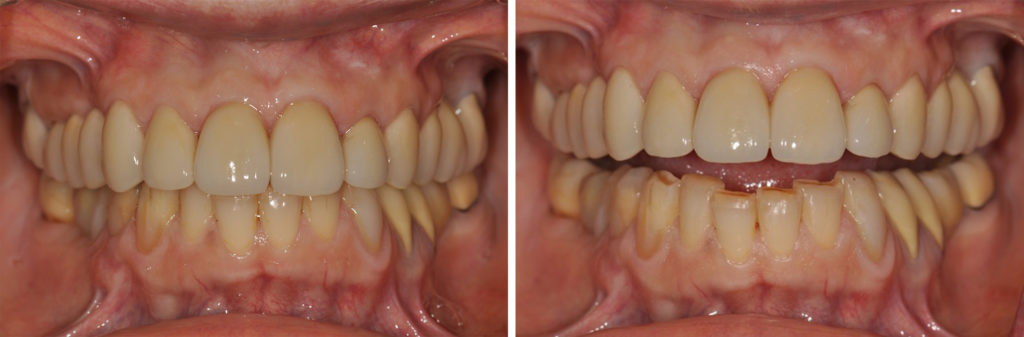

Fig. 8a à 8j : Résultat final

AVANT/APRÈS :

Un soin tout particulier doit être apporté à l’équilibration occlusale. L’équilibre occlusal est assuré, en OIM, par des contacts bilatéraux, simultanés et d’égale intensité sur les dents postérieures de canines à deuxièmes molaires (Fig. 9a et 9b). Les rapports inter-incisifs en OIM doivent laisser échapper une feuille de 9 microns d’épaisseur (Fig. 9c). Les entrées et sorties de cycle masticatoires sont contrôlés par élimination des interférences entre les versants cuspidiens des dents postérieures d’une part, et des faces palatines des incisives maxillaires et les bords libres des incisives mandibulaires d’autre part.